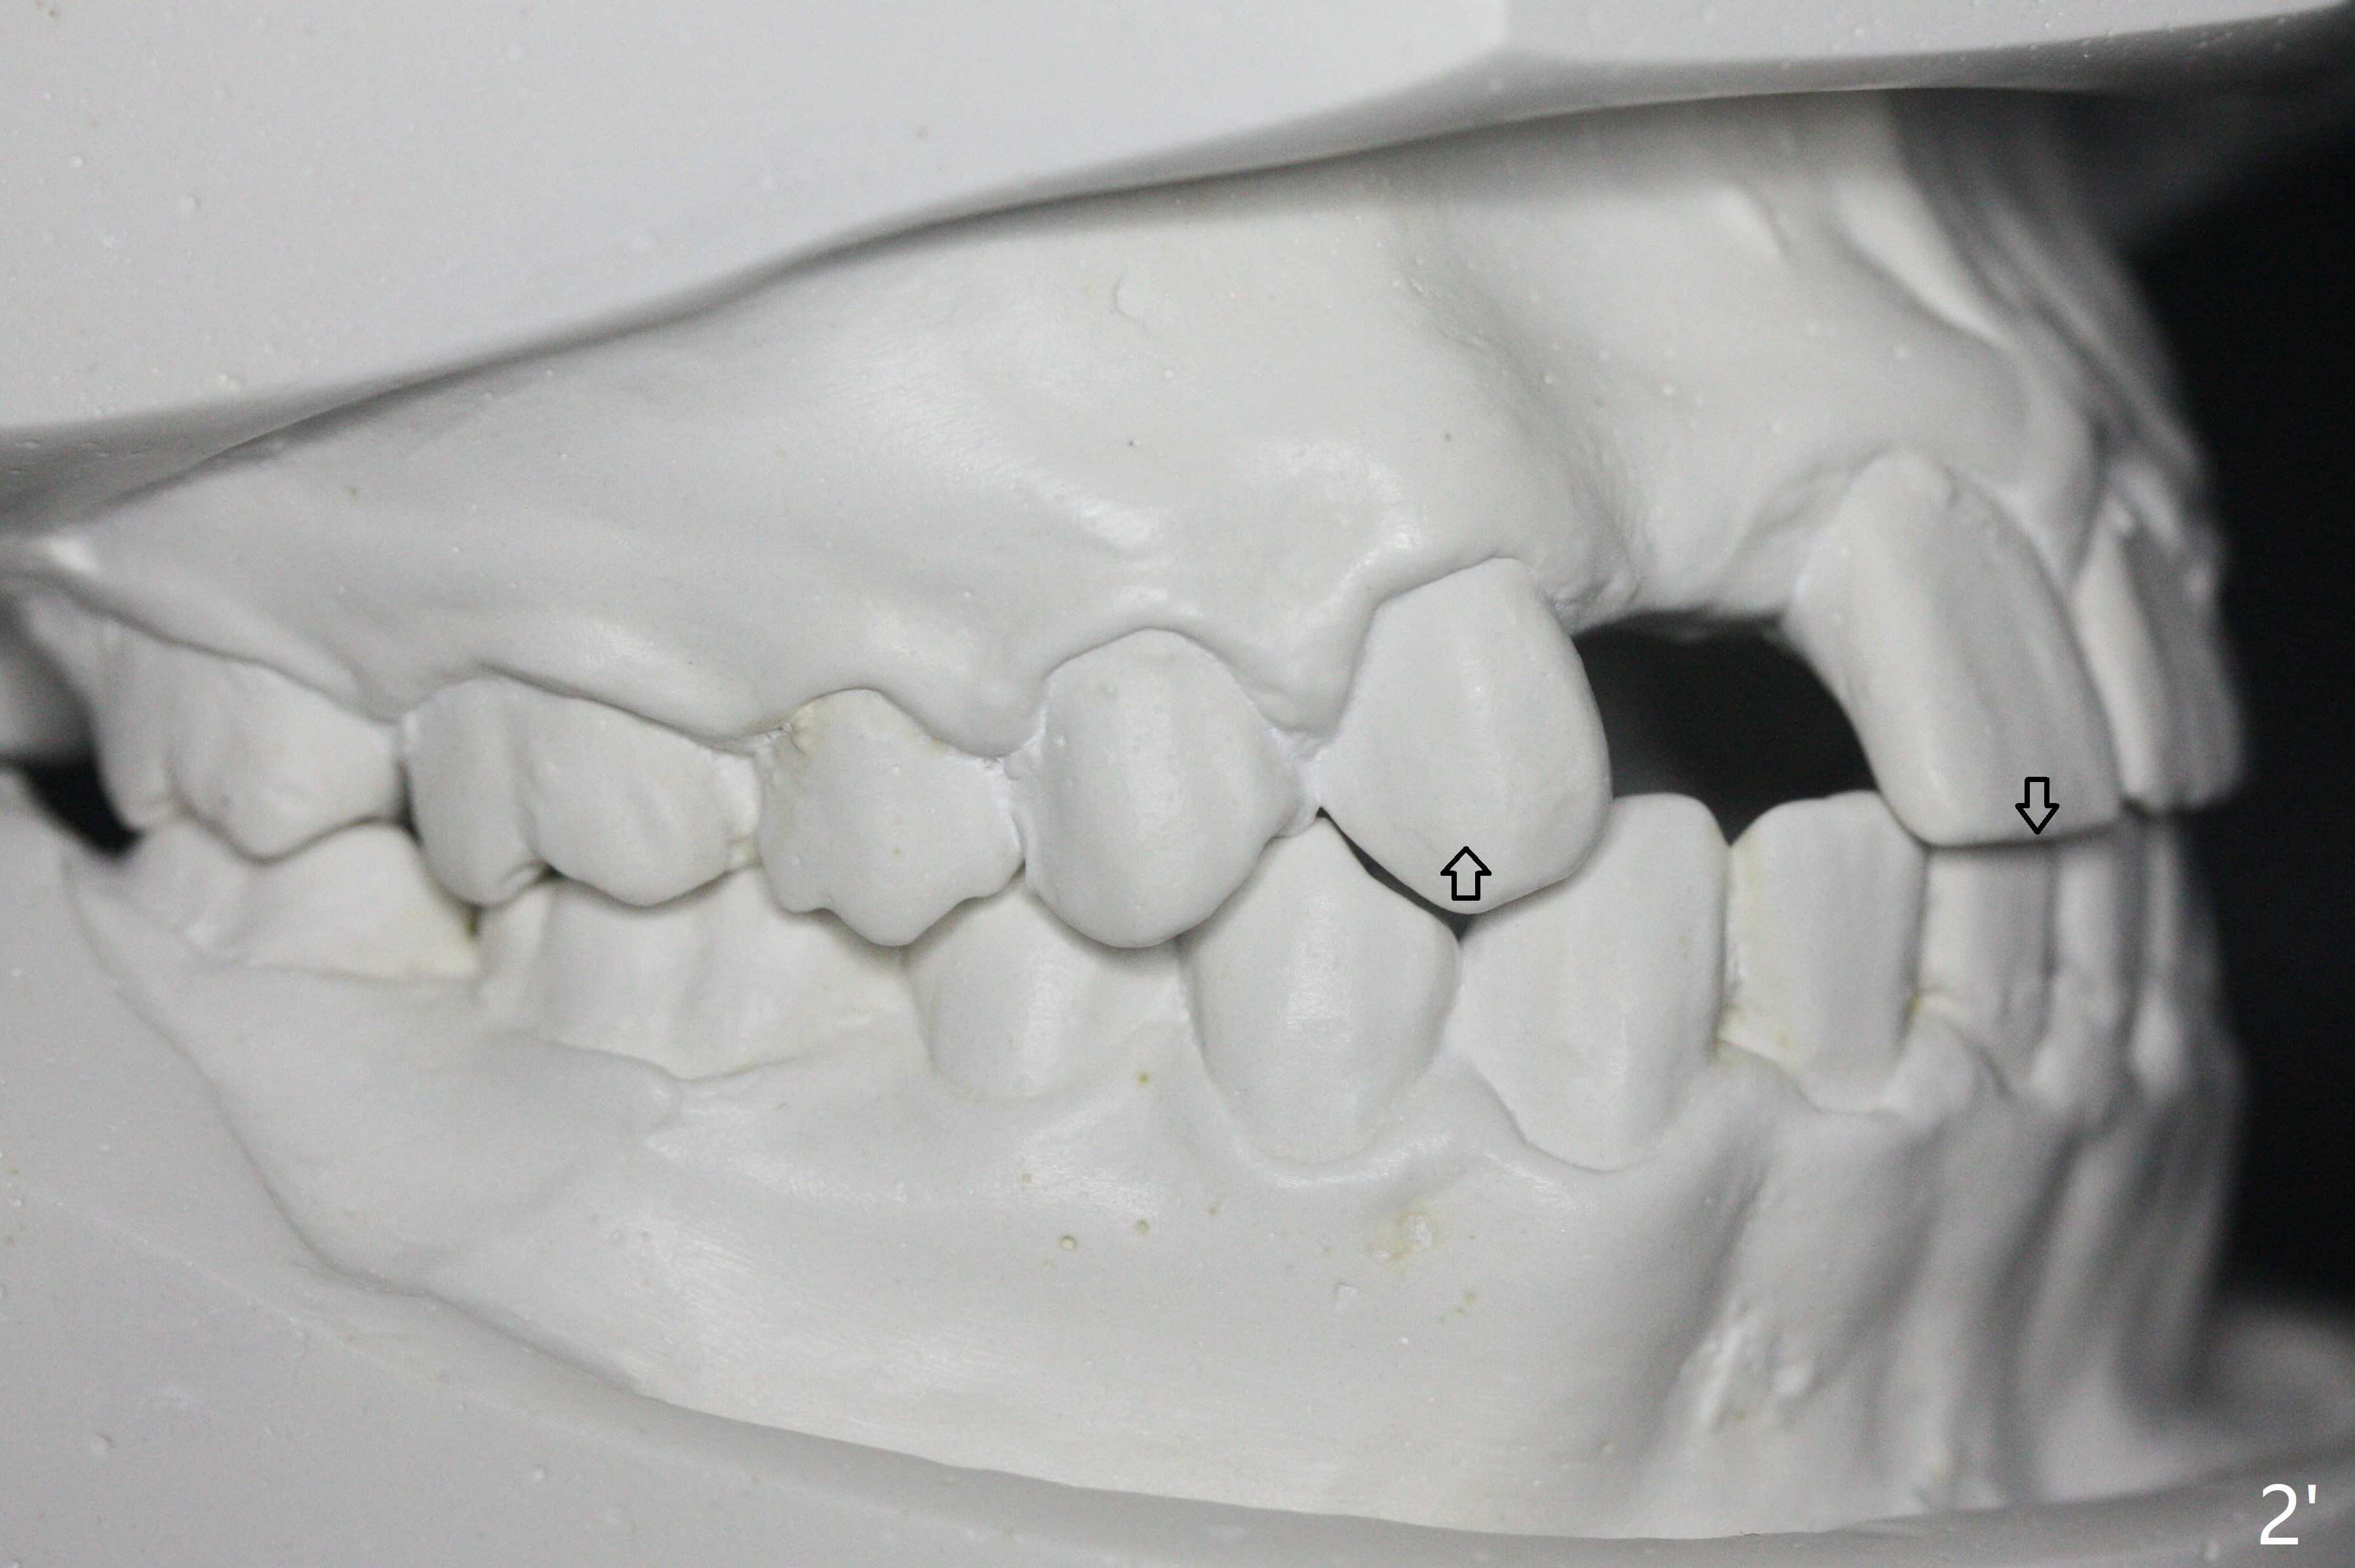

A 15-year-old man finishes orthodontic treatment for congenital missing lateral in 13 months. Molar Class I relationship remains the same (Fig.1,2,4,5). The upper diastemata mesial to 4s (Fig.4,7") close with correction of the upper midline deviation (Fig.2'-4'). The kid is unpleased with the elongated UR1 (Fig.2',3'). In fact it is a preexisting condition (Fig.2 arrow, 2"), but bracket placement at UR1 should have been overcorrected (incisal placement, Fig.3"). The intrusion should be done (Fig.4") before closure of the diastemata, since anchorage may be weakened when the separation between UR1 and 3 increases by using open coil spring. To prevent immediate relapse of the diastema between the upper central incisors, a fixed retainer is placed lingual before debracketing (Fig.6,6',6").